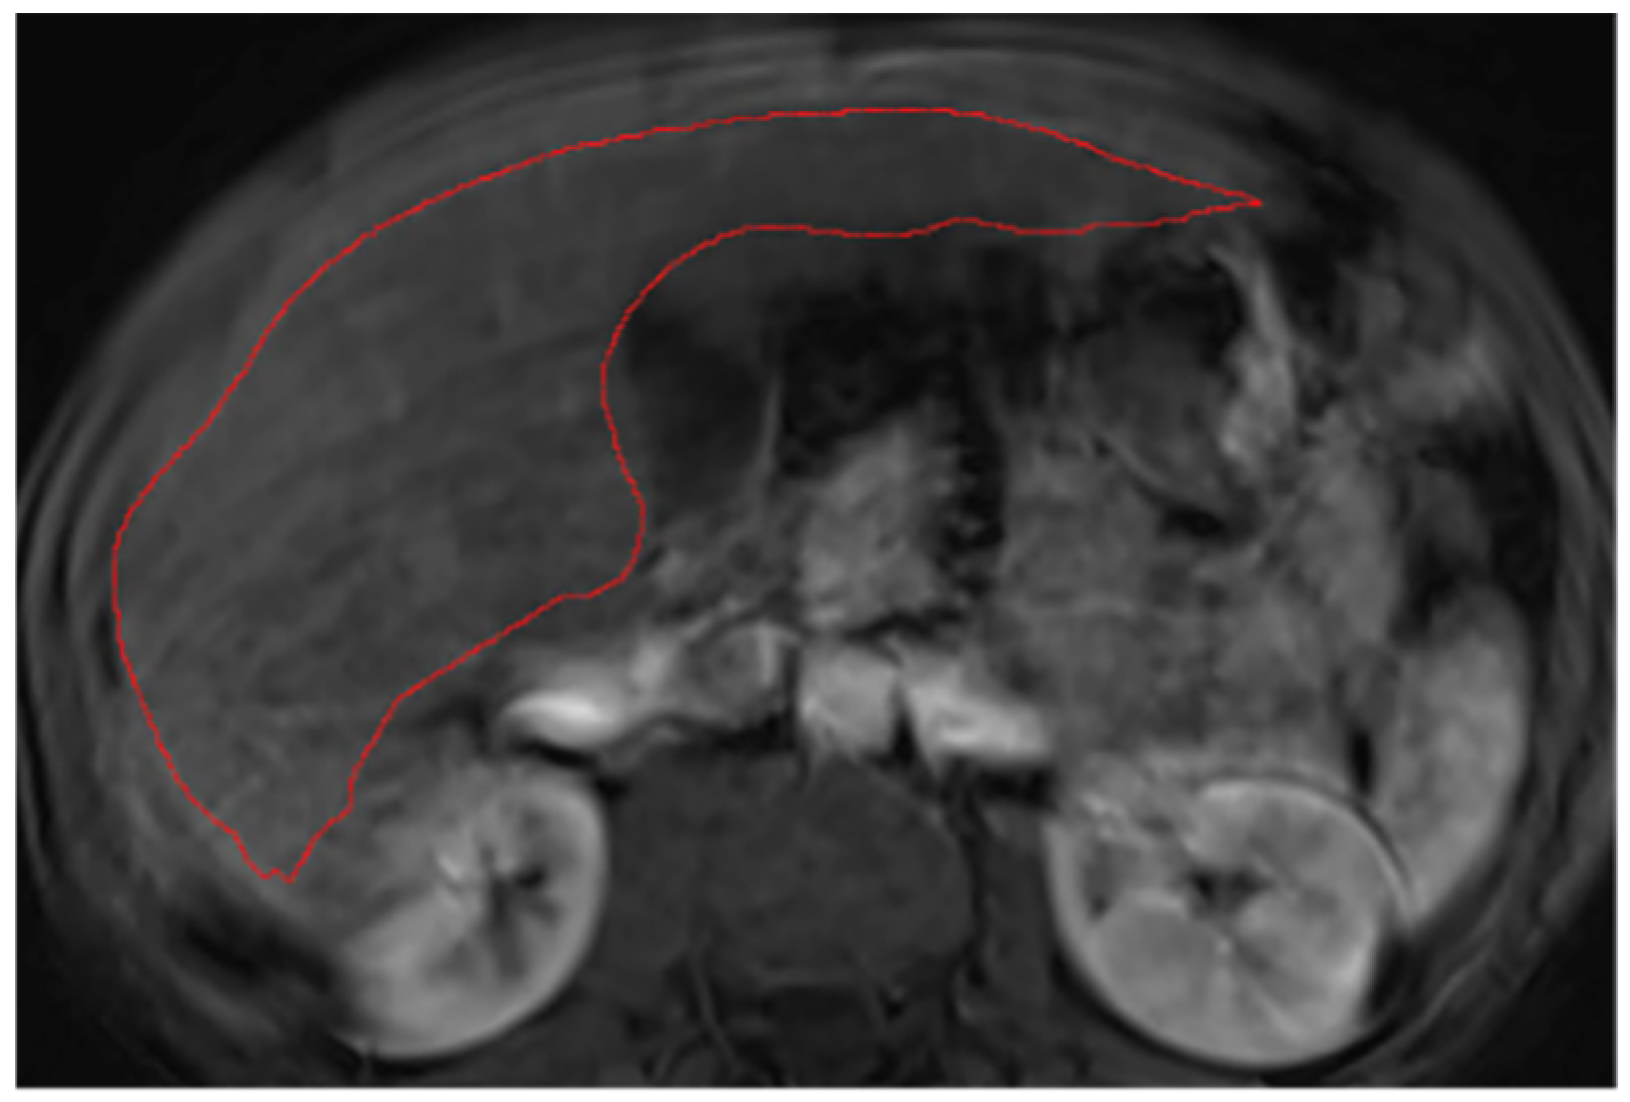

2.2. Liver Segmentations and Protocol

Appendix A.2. Hepatic Hilum Segmentation

Appendix A.3. Vascular Segmentation

Appendix A.4. Ligaments Segmentation

Appendix A.5. Multi-Part Liver Parenchyma

Appendix A.6. Presence of Respiratory Artifacts

Appendix A.7. Ascites